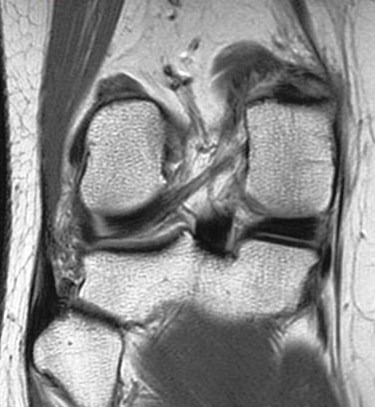

Figure 1 for case Partial tear of the tendon of the medial head of the gastrocnemius muscle ( RID2921 )

Figure 1

Partial tear of the tendon of the medial head of the gastrocnemius muscle ( RID2921 )